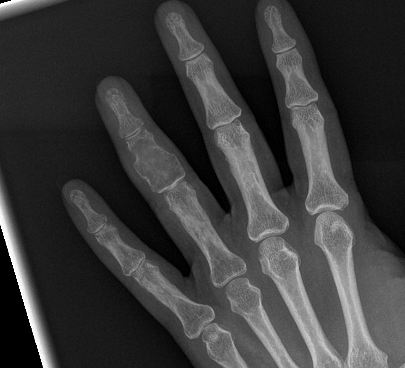

X-ray

Eccentric, sharply demarcated lytic lesion

- no sclerosis around lesion

- narrow zone of transition

- metaphysis, extending into epiphysis

- no mineralization

5% small bones hand and feet